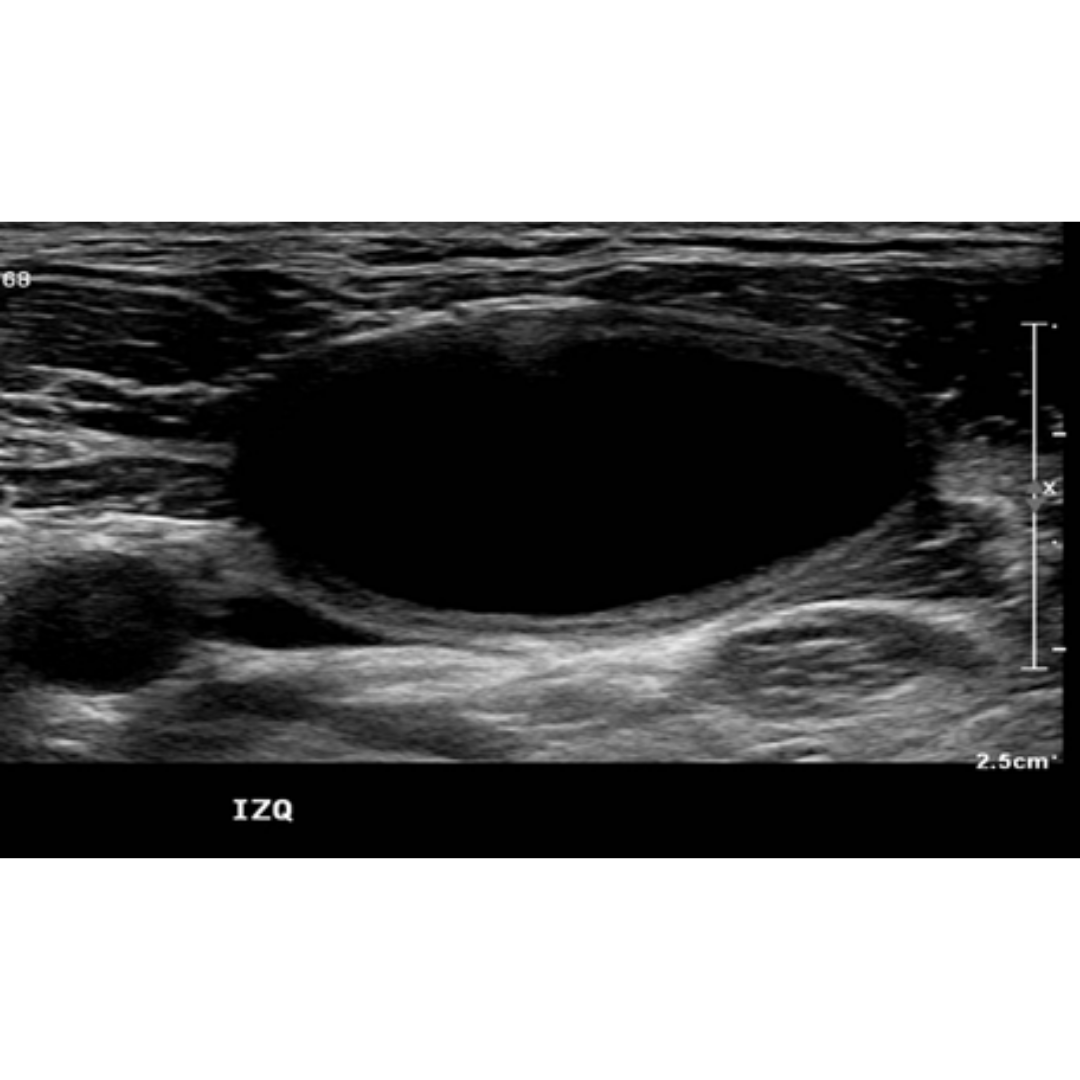

Linfoceles

Las linfoceles son acumulaciones quísticas linfáticas subcutáneas revestidas por un saco endotelial. Pueden surgir como una complicación por la disección de linfonodos cervicales, asociado a la tiroidectomía. Esta lesión puede tener una incidencia de 1-6%. Suelen controlarse bajo Ecografía hasta su completa desaparición espontánea.

Hallazgos ecográficos:

Se observa colección anecogénica, sin vascularización al Doppler, bien delimitada, con cápsula periférica, habitualmente ubicado entre segmentos cervicales III y IV.

Figura 3. Linfocele en compartimento cervical izquierdo.